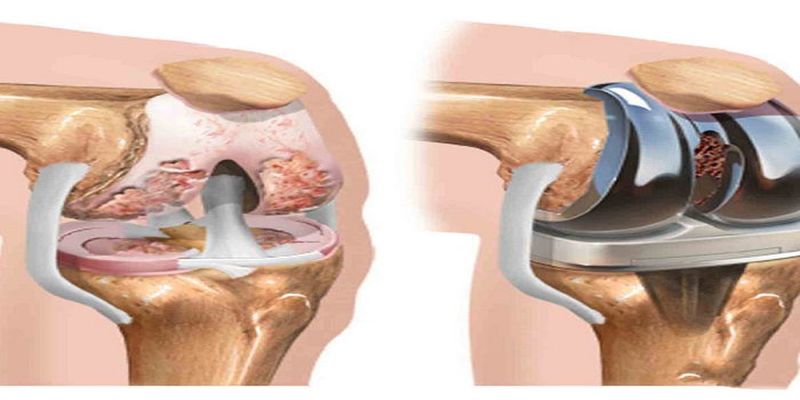

Kök hücre tedavisi

Yüzyılın tedavisi , ameliyatsız tedavi , Narkoz Yok , Ayni Gün Taburcu , %97 iyileşme garantisi , ülkemizde kök hücre tedavisini ilk yapan klinik biziz, dokuz yıldır bu tedaviyi başarı ile yapıyoruz.